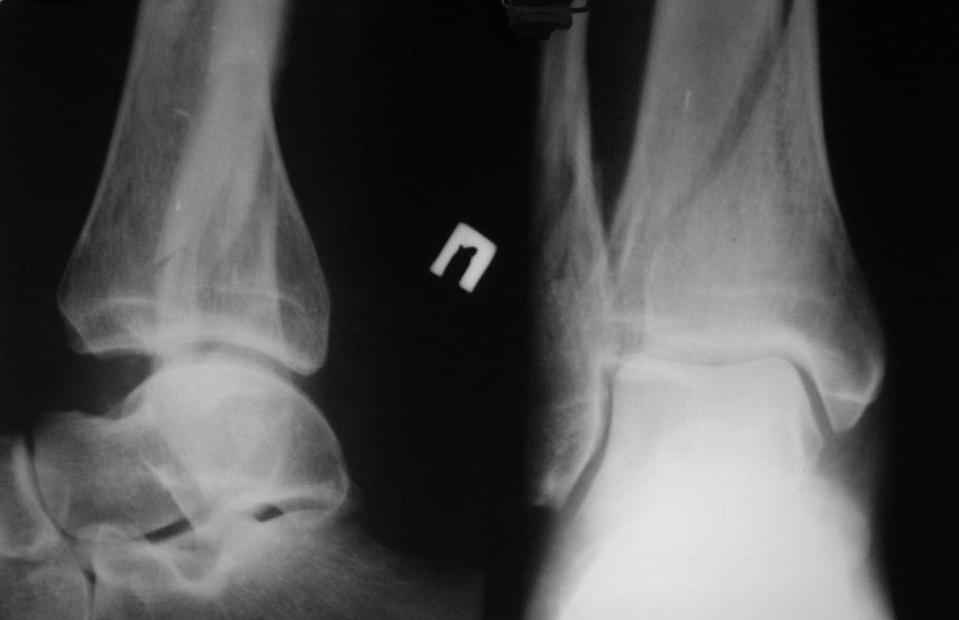

прошу прощения за то, что забыл приложить снимки